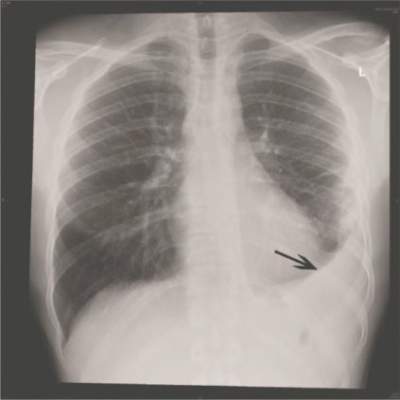

Viral infections appear to be the primary cause of pneumonia that results in hospitalization, according to a Centers for Disease Control and Prevention study of five urban hospitals in Chicago and Nashville, Tenn.

From January 2010 through June 2012, 2,259 patients hospitalized for community-acquired pneumonia (CAP) had both radiographic evidence of disease and specimens for bacterial and viral testing. A pathogen was detected in just 853 (38%). One or more viruses were detected in 530 (23%), bacteria in 247 (11%), bacterial and viral pathogens in 59 (3%), and fungal or mycobacterial pathogens in 17 (1%). The findings indicate the annual incidence of community-acquired pneumonia requiring hospitalization is about 25 cases per 10,000 adults, with the highest rates among adults 65-79 years old (63 cases per 10,000) and 80 years or older (164 cases per 10,000).

Courtesy NIH National Library of Medicine/Institute for Physical Education and Sport, University of Malta, Malta/Creative Commons License

The annual incidence of community-acquired pneumonia requiring hospitalization is about 25 cases per 10,000 adults, according to CDC researchers.

The most common pathogens were rhinovirus in 9% of patients, influenza virus in 6%, and Streptococcus pneumoniae in 5%, which was the most commonly detected bacterium (N. Engl. J. Med. 14 July 2015 [doi:10.1056/NEJMoa1500245]).

CAP is thought to be caused most often by S. pneumoniae and other bacteria; the fact that viruses were more frequently detected “probably reflects the direct and indirect benefit of bacterial vaccines,” but also “relatively insensitive diagnostic tests,” said the investigators, led by CDC medical epidemiologist Dr. Seema Jain.

The project, dubbed the Etiology of Pneumonia in the Community (EPIC) study, “adds to the growing evidence of the contribution of viruses to hospitalizations of adults.” It also suggests “that improving the coverage and effectiveness of recommended influenza and pneumococcal vaccines and developing effective vaccines and treatments for human metapneumovirus, respiratory syncytial virus, and parainfluenza virus” – also found in study patients – “could reduce the burden of pneumonia among adults,” the researchers said.

The work matters because “the last U.S. population–based incidence estimates of hospitalization due to community-acquired pneumonia were made in the 1990s, before the availability of the pneumococcal conjugate vaccine and more sensitive molecular and antigen-based laboratory diagnostic tests. Thus, contemporary population-based etiologic studies involving U.S. adults with pneumonia are needed,” they noted.

Blood, urine, and respiratory cultures; serologic testing; antigen detection; molecular diagnostics, and chest x-rays were all used to find the cause of disease. The fact that infections were found in just 38% of the patients could have something to do with the team’s “inability to obtain lower respiratory tract specimens, antibiotic use before specimen collection, [and] insensitive diagnostic tests for known pathogens,” among other problems, they said.